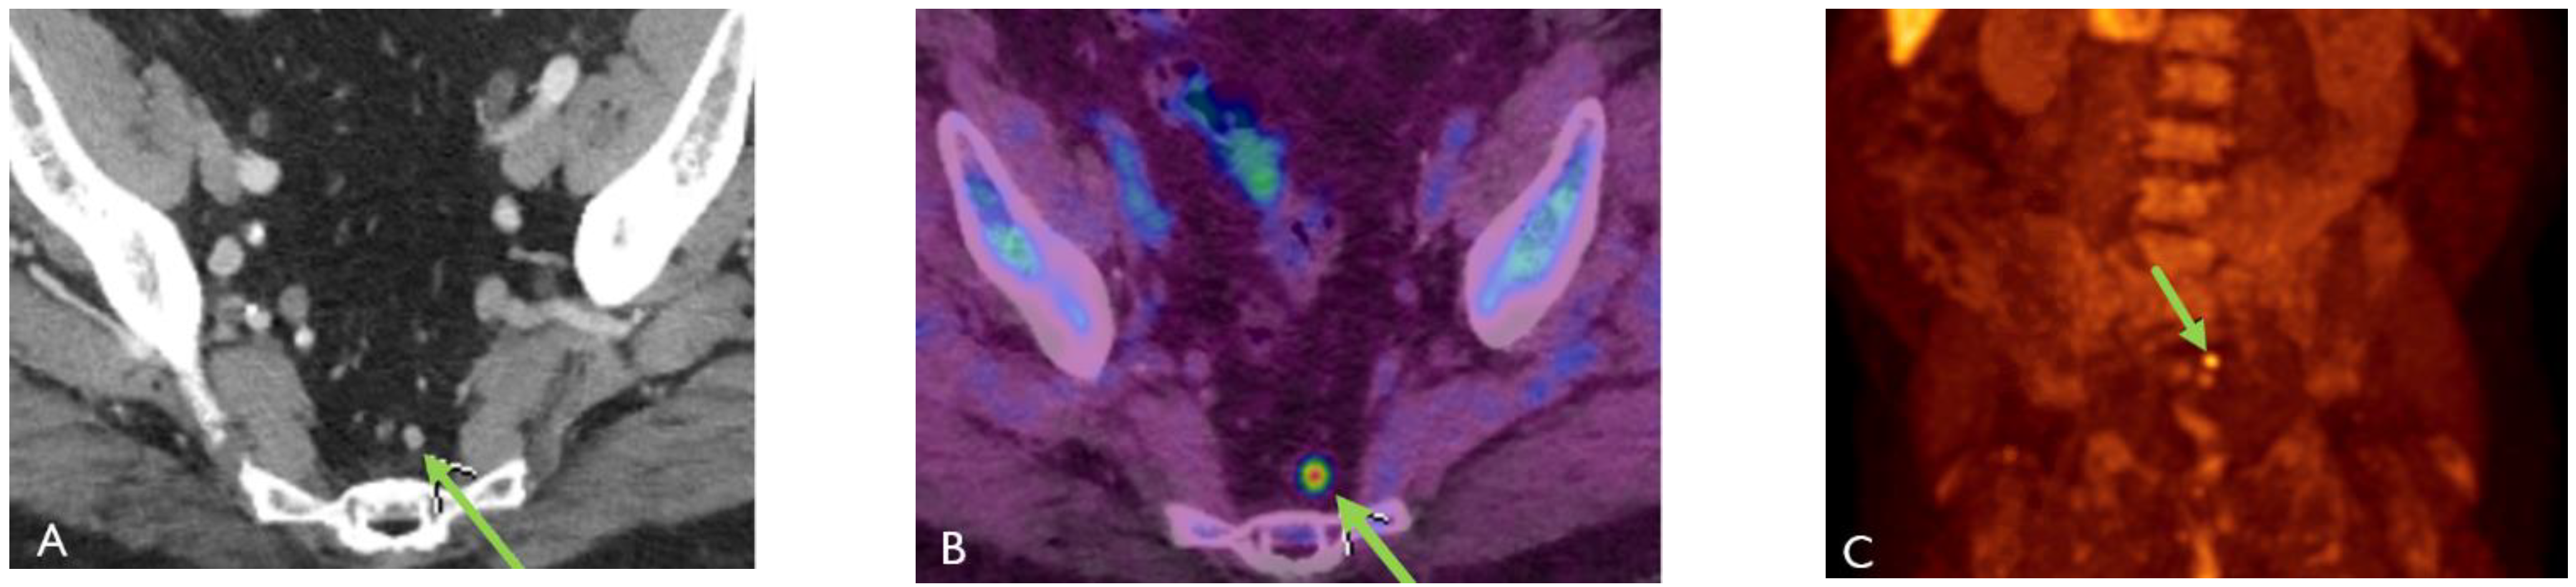

Detection of Loco-Regional Disease and Distant Metastases

- Barbosa, F.G.; Queiroz, M.A.; Nunes, R.F.; Viana, P.C.C.; Marin, J.F.G.; Cerri, G.G.; Buchpiguel, C.A. Revisiting Prostate Cancer Recurrence with PSMA PET: Atlas of Typical and Atypical Patterns of Spread. Radiographics 2019, 39, 186–212. [Google Scholar] [CrossRef]